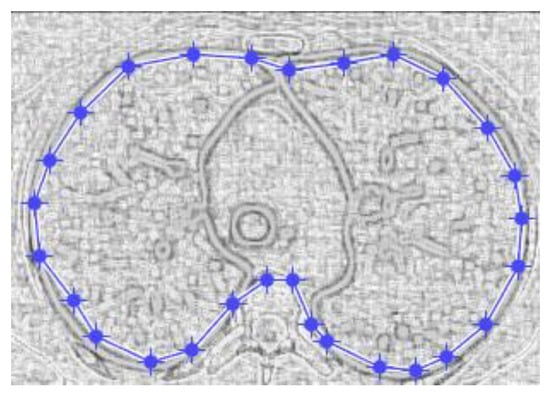

Figure 9 and Figure 10 show the original CT lung image, respectively, and the defined mask for the COVID-19 lung CT image, framed in a blue border in Figure 10.

Figure 10 presents the applied mask across the COVID-19 lung CT image, framed in a blue colour border.

Figure 17 and Figure 18 show the original non-COVID-19 CT pulmonary picture, respectively, and the defined mask for the non-COVID-19 CT pulmonary picture, framed in a blue border, Figure 18.

Figure 18 presents the applied mask across the non-COVID-19 CT lung image, framed in a blue colour border.

Figure 10. Mask applied for COVID-19 lung image.

Figure 18. Applied mask for a non-COVID-19 lung image.